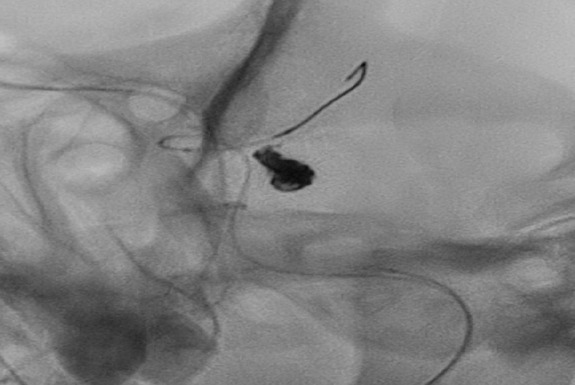

അമലയിൽ ബലൂൺ-അസിസ്റ്റഡ് കോയിൽ എംബൊലൈസേഷൻ വഴി പൊട്ടിയ ബ്രെയിൻ ആന്യുറിസം വിജയകരമായി ചികിത്സിച്ചു